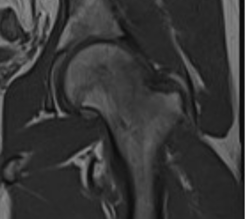

Femur başı osteonekrozu kemiğe giden kan akışının bozulması sonucu oluşur. Kemik iliği hücreleri ve osteositlerin (olgun kemik hücreleri) ölümüyle karakterizedir.